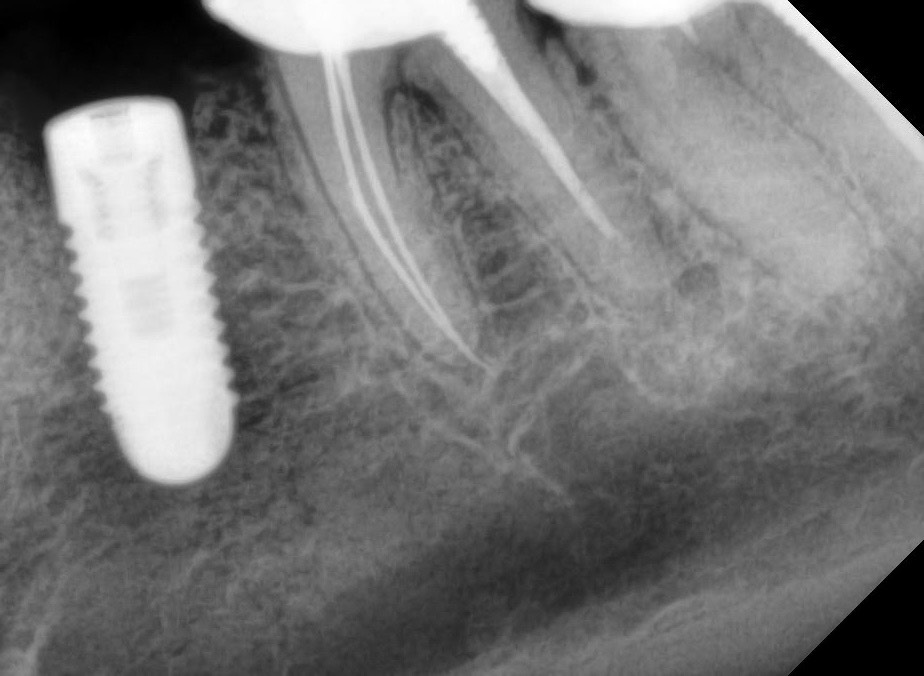

Панорама до удаления и установки импланта. Прицельные сделали вчера до депульпирования 34.

Решение о депульпировании принимается скорее на основании клинического осмотра, снимки тут имеют вспомогательное значение

судя по предоставленным снимкам явных причин депульпировать 3.4 зуб я не вижу